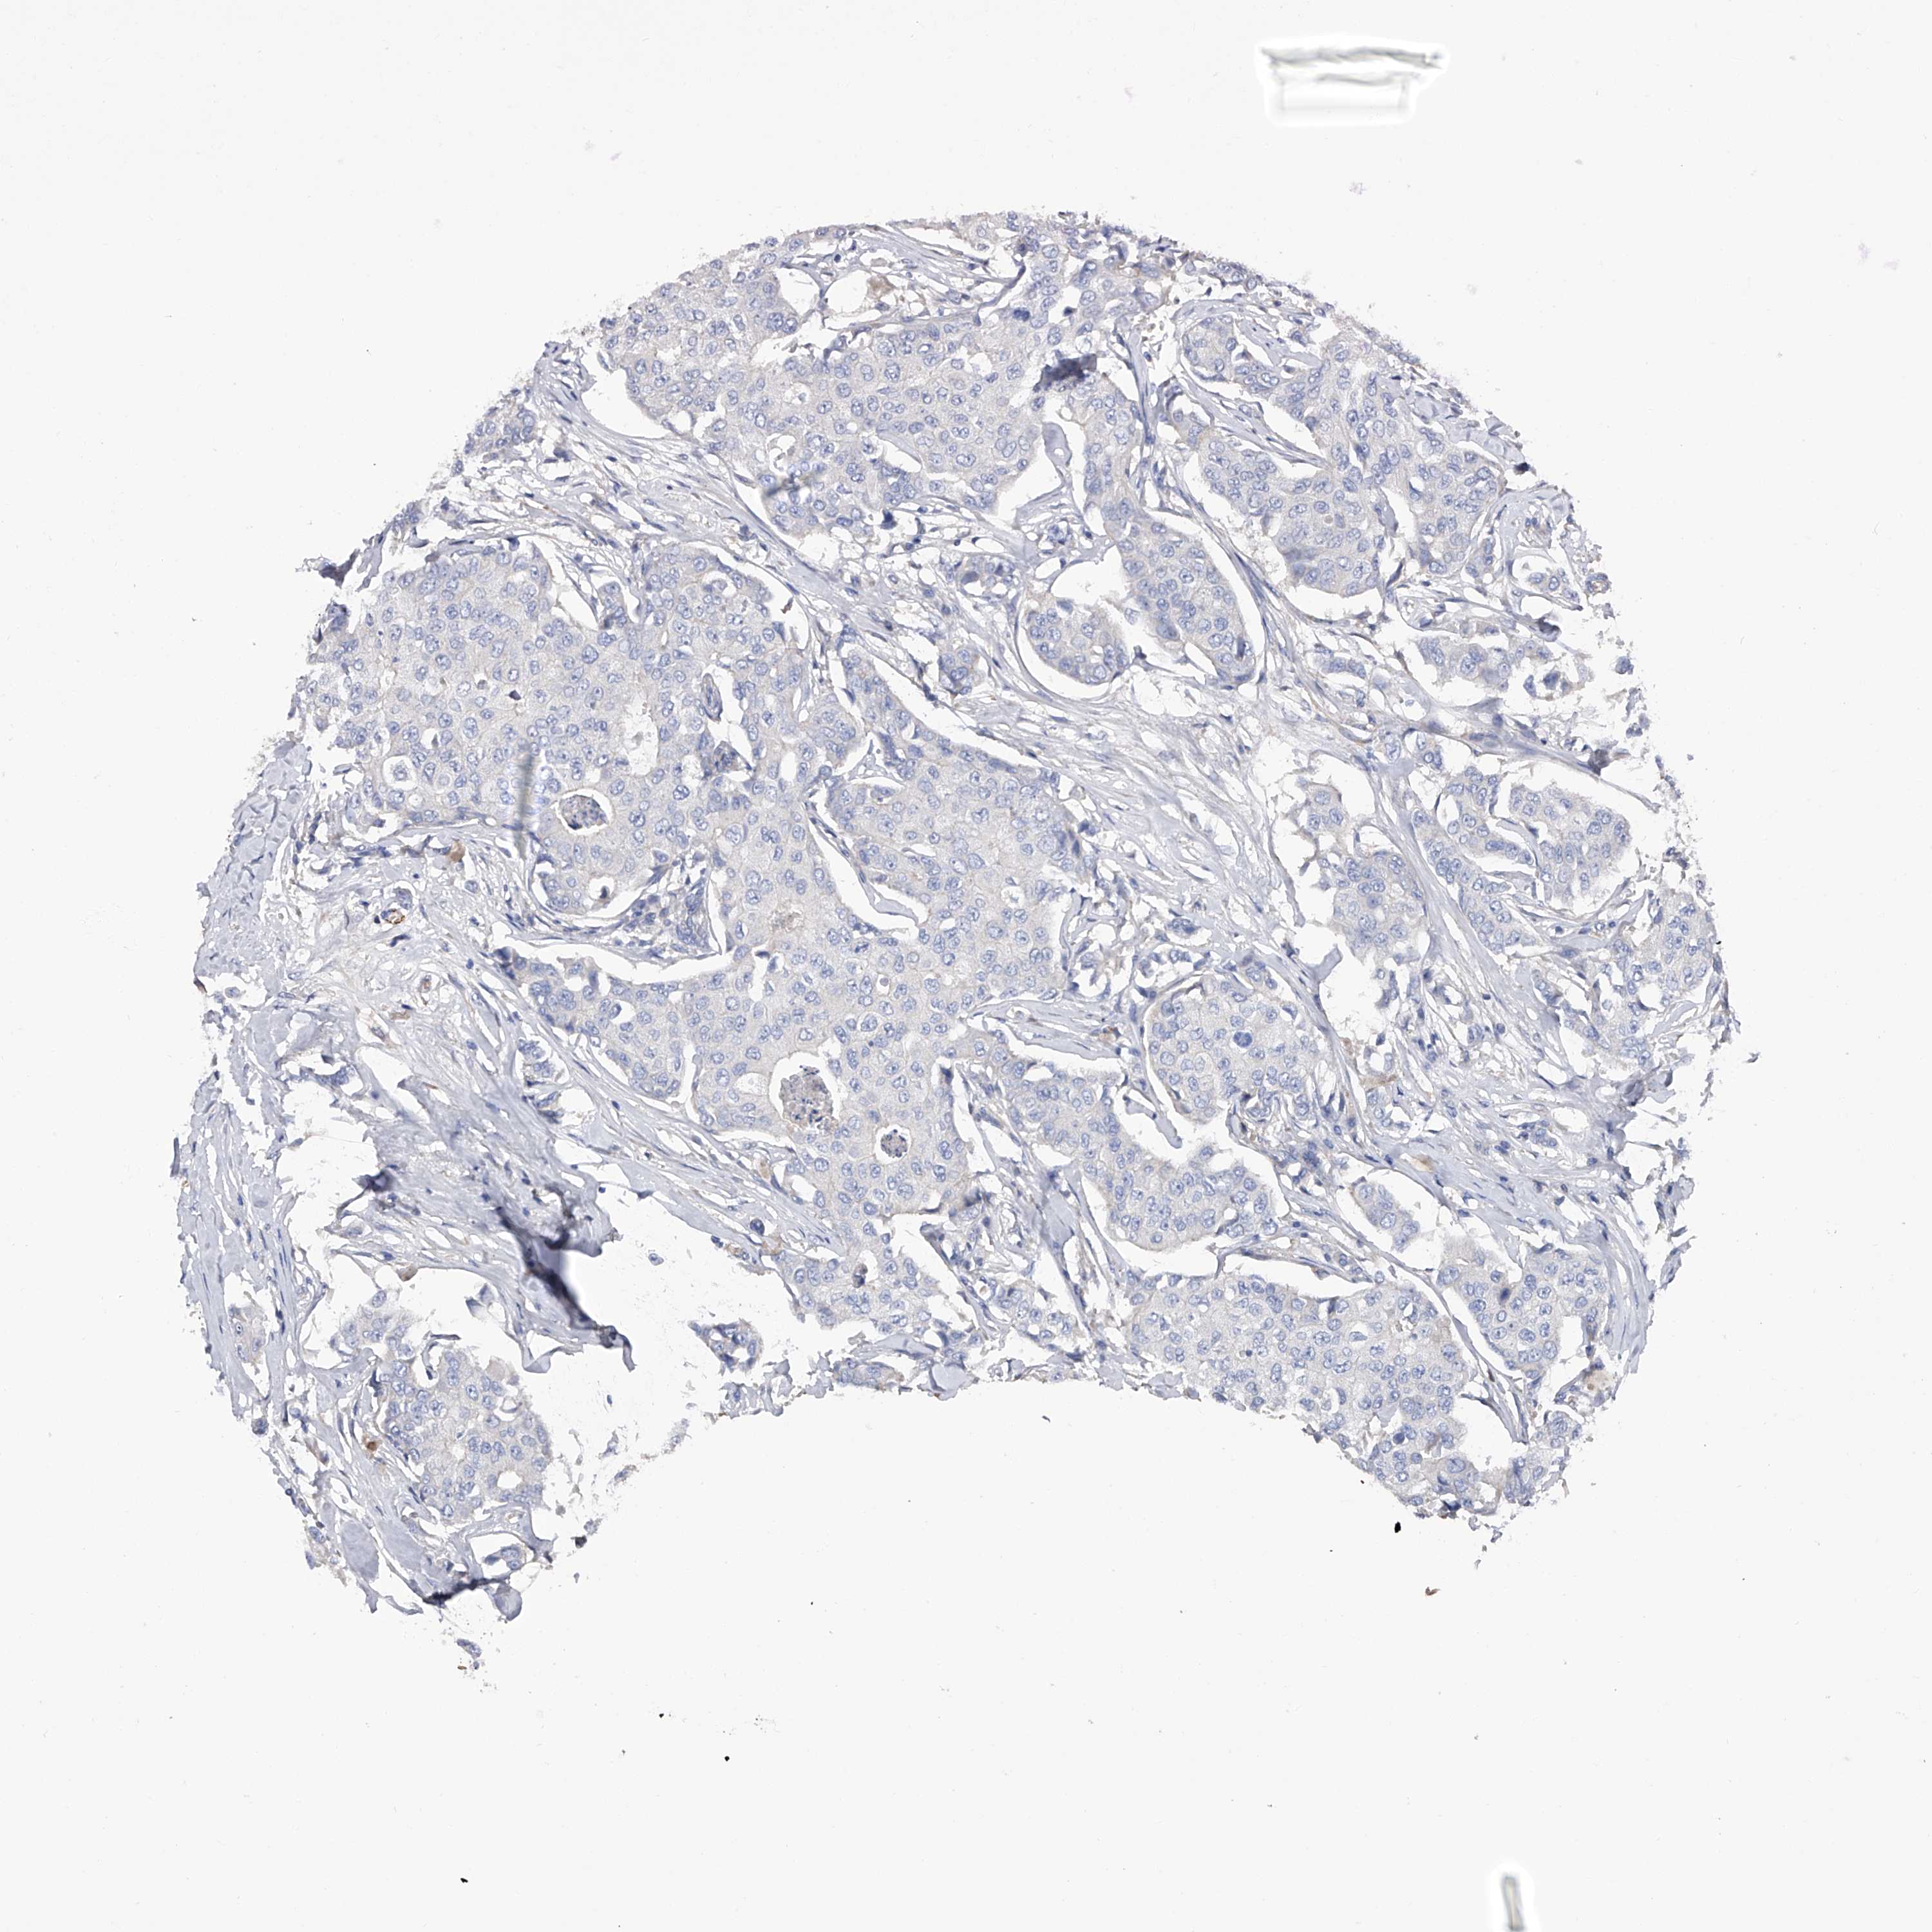

CANCER BREAST CANCER Show tissue menu

BRCA TCGA BRCA VALIDATION PROTEIN EXPRESSION

Breast cancer

Human cancer

Breast invasive carcinoma